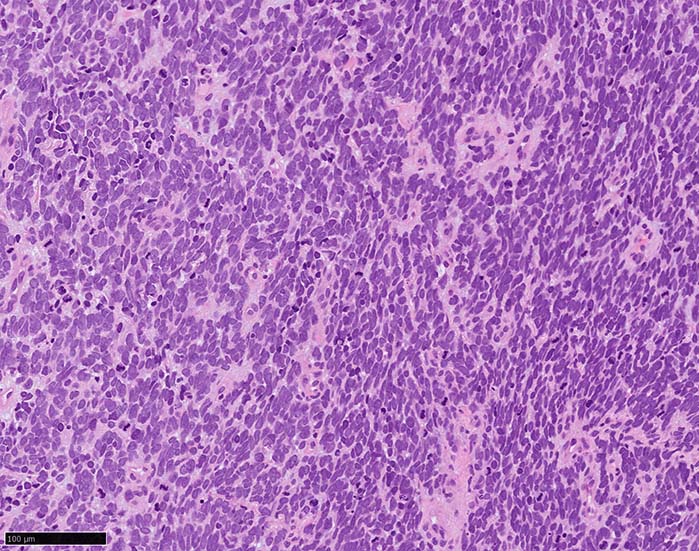

典型的な腫瘍細胞は円形, 卵円形の比較的均一な形態で「salt-and-pepper」と称される微細顆粒状クロマチンを有する小型円形核をもつ. MCPyV陽性例が均一な小型円形核を呈する傾向があり, 陰性例では, 核多形性が目立つととする報告がある.

trabecular type, intermediate type, samll cell typeの3パターンの組織型に分類されているがしばしば混在している.

- trabecular typeは円形から多稜形の腫瘍細胞が索状に配列, 3形のなかで腫瘍細胞がもっとも大きく, 円形核と比較的豊富な細胞質をもつ.

- small cell typeは濃いクロマチン, 多形性を示す核をもつN/C比大の小型腫瘍細胞がびまん性に増殖する.

- intermediate typeではtrabecular, samll cell typeの中間の腫瘍細胞サイズを示す. 組織型としてはもっとも多い.

腫瘍内浸潤リンパ球/炎症細胞は多くの症例で認められる. リンパ球の腫瘍内浸潤は予後良好因子と報告されている. 16

HE

血管を間質にしてround cellsが索状に増殖する所見. rossett様配列がある. CK20は特徴的な dot-like patternを示す. クリックで大きな画像が見られます.